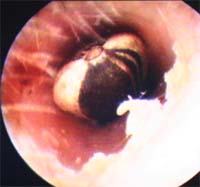

年長女児 母親が、右耳に白いもの を見つけて受診 直径6.5mm長さ5.5 耳垢が付いており、陳旧な お人形の一部 2019年10月21日  |